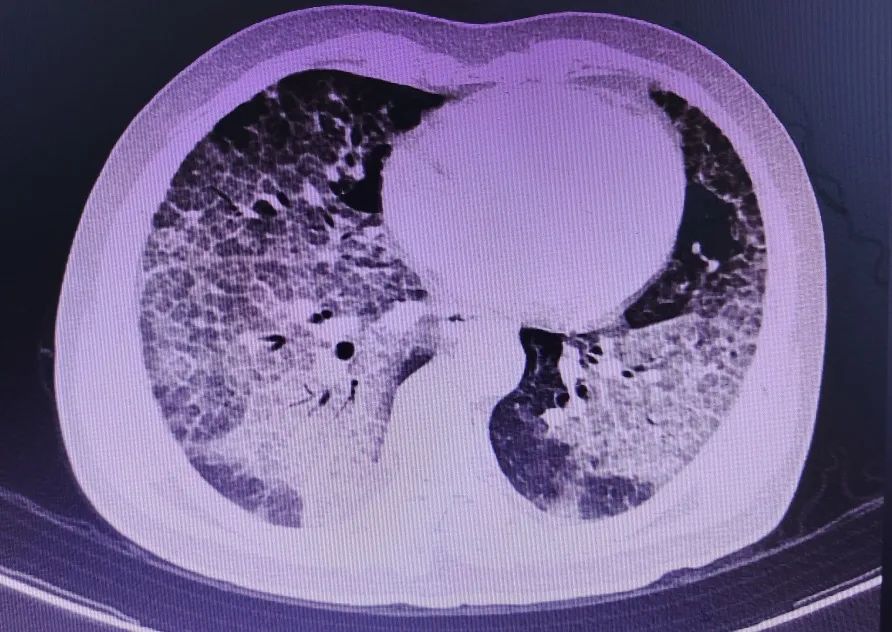

43岁的唐先生因“呼吸困难加重3月”于2023年4月13日来我院呼吸与危重症医学科住院治疗。患者曾从事隧道工作,高粉尘接触10余年,抽烟20年,每日20支。入院后完善胸部CT提示:“双肺弥漫性病变”。结合血气分析提示:I型呼吸衰竭,在高流量氧疗仪辅助通气治疗下(流速60l/min及氧浓度60%)血氧饱和度只能维持在85%左右。科室组织科内病例讨论,考虑“肺泡蛋白沉积症”可能,并制定诊疗计划。

图1为入院时CT 图2为灌洗、治疗后CT